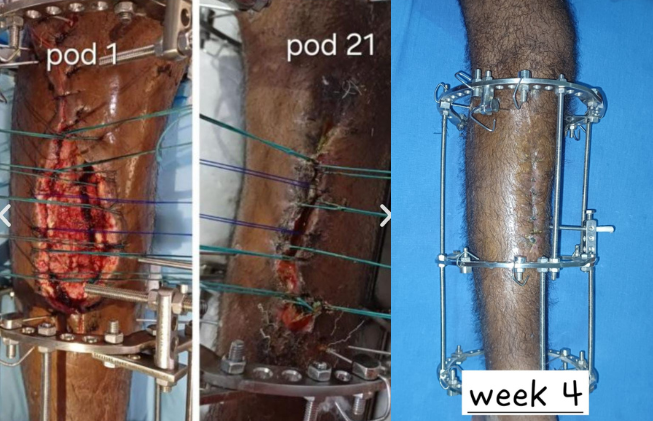

Ilizarov for malunited fracture with bad skin condition

Skin transport with ilizarov surgery